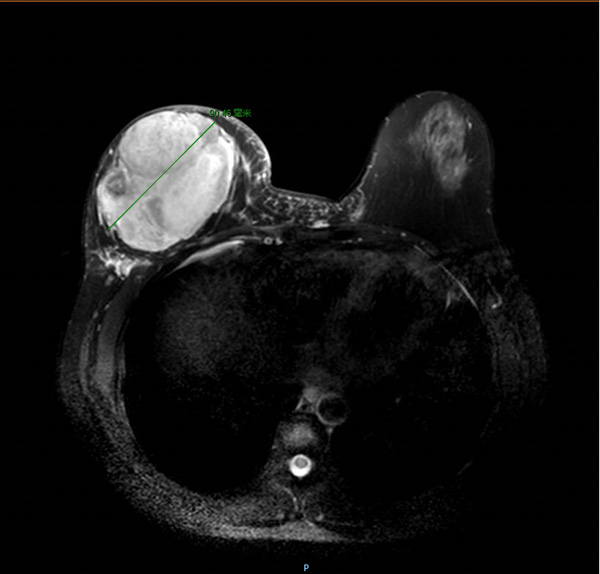

經了解病史、查體及輔助檢查等系統檢查,覃舒婷考慮譚右乳腫瘤為乳腺葉狀腫瘤復發,建議手術治療,切除右乳乳腺。

“為什么我的乳房要全部切掉!”譚及家屬前往醫生辦公室詢問。覃舒婷結合磁共振影像,耐心地為他們解惑。譚終于明白,如果不全部切除,她右乳的巨大腫瘤很可能再次復發。

譚還是無法接受切除一側乳房,這相當于毀了她的生活。覃舒婷能夠理解譚的擔憂,她與科室負責人莫軍揚副主任及科室的其他醫生商量后,給出了手術方案建議——右乳乳腺全部切除+假體植入手術,這樣既能最大程度地減少腫瘤復發,又能即刻重建乳房,維持對稱的乳房外形。

精細地測量與術前規劃后,譚女士的手術開始了。莫軍揚協同覃舒婷等醫生,徹底摘除了困擾譚女士數年的腫瘤。隨后,他們按照術前測量計算的乳房容積,選擇了最合適的假體植入物,即刻重建了一個與左側幾乎對稱的乳房。術后,經科室醫護團隊悉心照料,譚順利拔管出院。